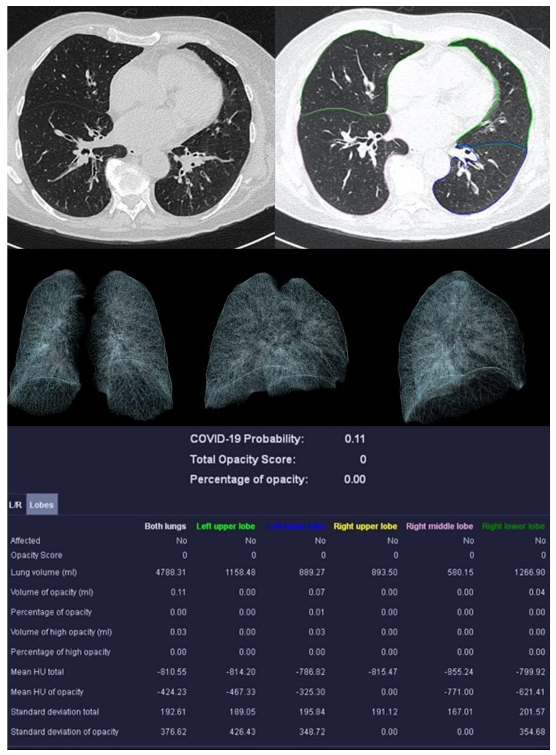

| Mean COVID-19 Probability ± SD | 0.80 ± 0.36 | 0.33 ± 0.4 | 0.55 ± 0.47 | 0.66 ± 0.44 |

| Mean LSS ± SD | 8 ± 5 | 5 ± 4 | 5 ± 6 | 0 ± 0 |

| Mean PO ± SD in % | 26.39 ± 23.22 | 12.52 ± 17.97 | 18.90 ± 26.27 | 0.05 ± 0.12 |

| Mean PHO ± SD in % | 6.42 ± 7.68 | 3.60 ± 4.47 | 5.86 ± 10.04 | 0.01 ± 0.02 |

| Mean HU total | −679.57 ± 112.72 | −750.12 ± 84.05 | −715.10 ± 37.28 | −820.18 ± 36.45 |

| Mean HU of opacity | −453.40 ± 170.46 | −427.39 ± 157.92 | −450.47 ± 115.38 | −416.18 ± 298.62 |